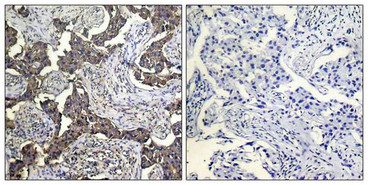

Immunohistochemical analysis of paraffin-embedded human breast carcinoma tissue using BAD (Phospho-Ser112) Antibody (left) or the same antibody preincubated with blocking peptide (right).

Immunohistochemical analysis of paraffin-embedded human Lung carcinoma tissue using BAD (Phospho-Ser112) Antibody (left) or the same antibody preincubated with blocking peptide (right).